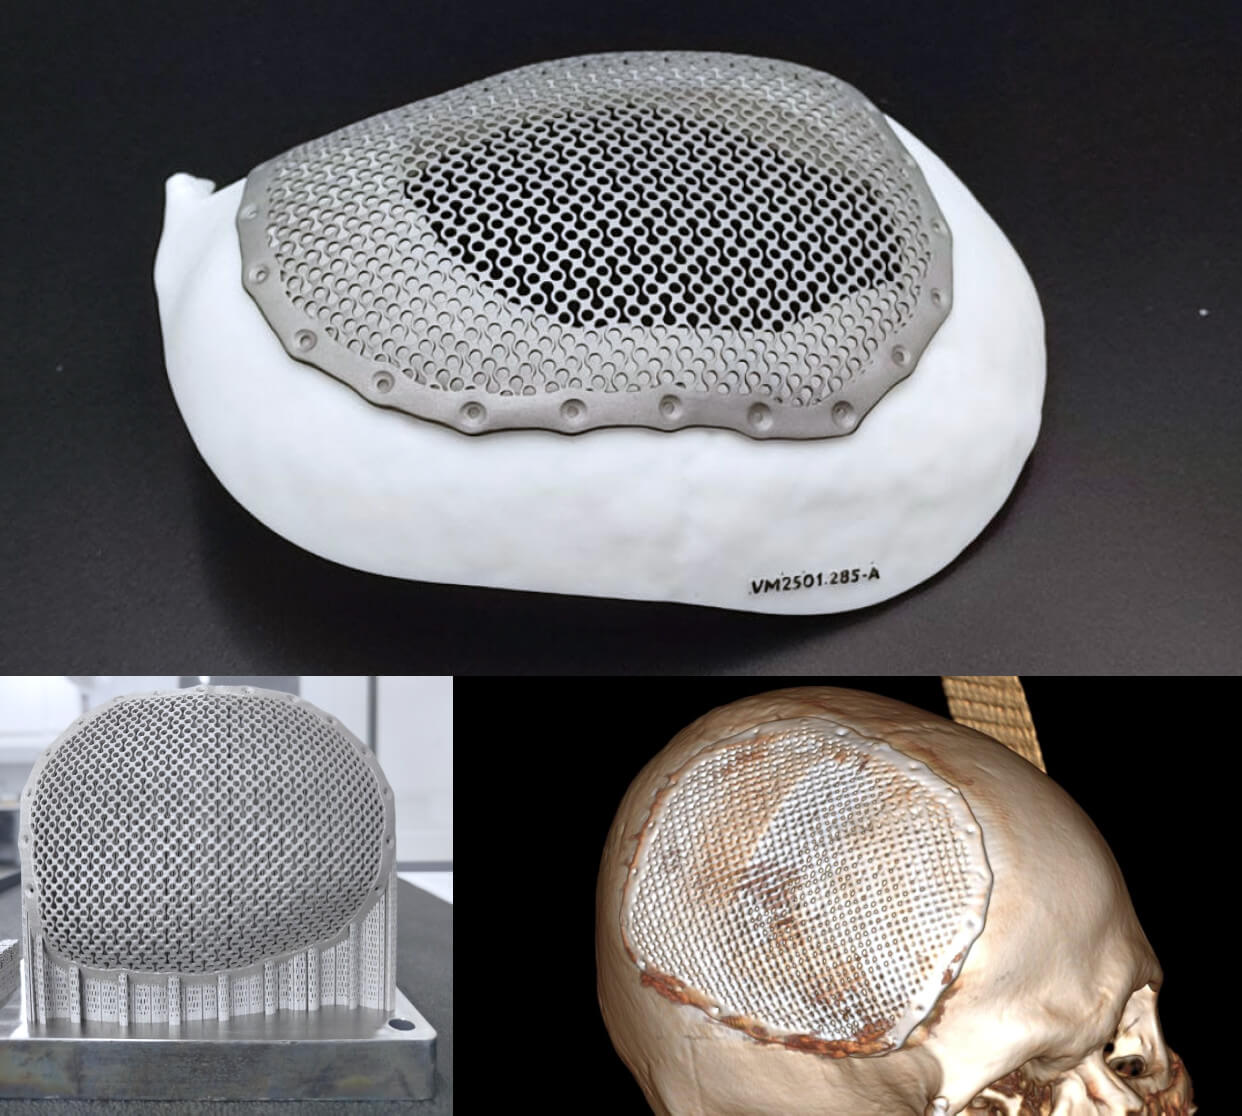

- Denys is a farmer and father of three. He could have gone abroad, but he chose to defend his country and his people. He suffered a severe head injury in a mine explosion. In Vinnytsia, he has now had a titanium plate implanted and is recovering well.

- In Vinnytsia, a seriously injured soldier received a custom-made skull plate. He now has a good chance of a speedy recovery.